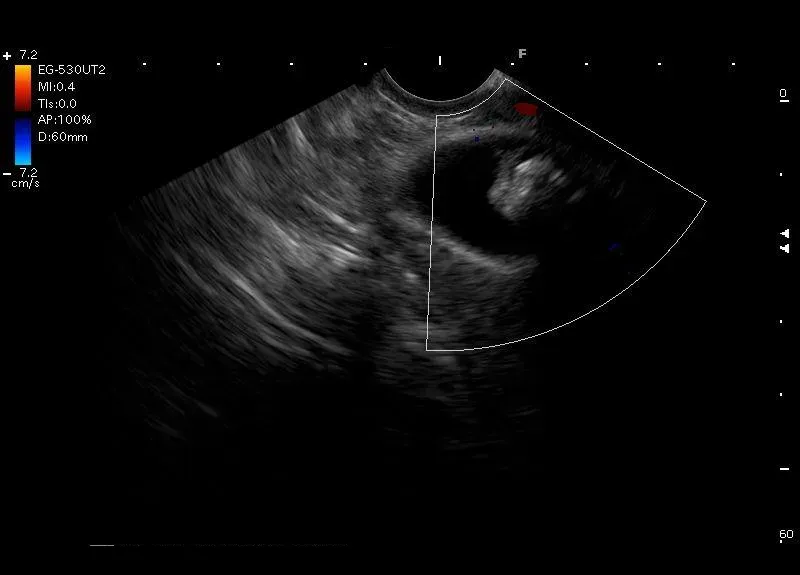

Hiperechogeniczna zmiana z cieniem akustycznym, bez przepływu naczyniowego w opcji Doppler, widoczna w świetle obkurczonego pęcherzyka żółciowego - złóg w pęcherzyku żółciowym